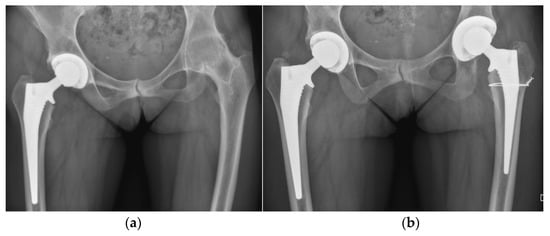

5.5. Hip

- Trebše, R.; Valič, M.; Savarin, D.; Milošev, I.; Levašič, V. Survival Rate of Total Hip Replacements with Matched and with Mixed Components with 10.7 Years Mean Follow-Up. Hip Int. J. Clin. Exp. Res. Hip Pathol. Ther. 2022, 32, 32–38. [Google Scholar] [CrossRef] [PubMed]

- Brumat, P.; Pompe, B.; Antolič, V.; Mavčič, B. The Impact of Canal Flare Index on Leg Length Discrepancy after Total Hip Arthroplasty. Arch. Orthop. Trauma Surg. 2018, 138, 123–129. [Google Scholar] [CrossRef]

- Brumat, P.; Mihalič, R.; Benulič, Č.; Kristan, A.; Trebše, R. Patient-Specific Template and Electromagnetic Navigation Assisted Bilateral Periacetabular Osteotomy for Staged Correction of Bilateral Injury-Induced Hip Dysplasia: A Case Report. J. Hip Preserv. Surg. 2021, 8, 192–196. [Google Scholar] [CrossRef] [PubMed]